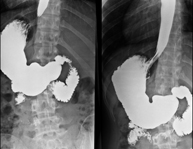

Prova diagnòstica que consisteix en obtenir imatges radiològiques en moviment de l'esòfag, estómac i duodè mitjançant l'ús de raigs X (fluoroscòpia) i d'un contrast opac baritat que s'administra per via oral. - Trànsit intestinal

Prova diagnòstica que consisteix en obtenir imatges radiològiques en moviment de l'esòfag, estómac, duodè i intestí prim mitjançant l'ús de raigs X (fluoroscòpia) i d'un contrast opac baritat que s'administra per via oral. - Ènema opac doble contrast

Prova diagnòstica que consisteix en obtenir imatges radiològiques de l'intestí gros (còlon i recte) mitjançant l'ús de raigs X. S'utilitza un contrast opac que s'administra a través del recte en forma d'ènema i també s'introdueix aire per expandir el còlon.